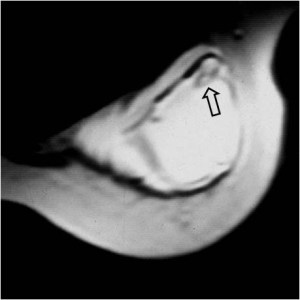

Signo de rotura de prótesis mamaria de silicona, visto en la resonancia magnética. Aparece una línea hipointensa separada de la cápsula fibrosa y plegada sobre sí (con la forma de una lágrima) -flecha-, por fuera de la cual se filtra la silicona libre (hiperintensa).

En este enlace encontrarás un póster del Congreso Europeo de Radiología de 2013 sobre hallazgos en RM sobre implantes de silicona: